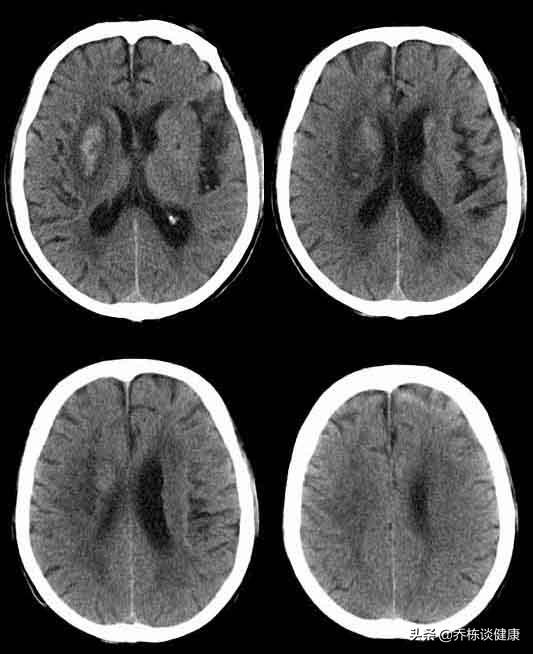

めまいは、さまざまな疾患の一般的な臨床症状であり、めまいの症状が出た後は、病院に行って、器質的な疾患を除外するために詳しい検査をしなければならない。例えば、頭蓋内腫瘍、頸部脊柱管の職業性病変などです。脳CTと血圧に問題がなければ、頭蓋内病変はなく、高血圧や低血圧の原因もありません。

めまいは、低血圧や高血圧の問題を除外するために血圧が正常であることが確認されているが、これらのタイプの問題がめまいを引き起こす可能性は低い。また、脳のCTが正常であることから、頭蓋内の病変が除外され、少なくとも大きな病気のリスクによる問題を遅滞なく軽減することができる。

第四に、脳の病気や腫瘍、脳卒中もめまいの原因になる。

脳への血液供給が低下することでめまいが起こるが、このような状態は通常血管狭窄で見られ、通常の頭部CTでは見ることができず、頸部血管超音波検査や頭蓋内血管ドップラー超音波検査で明らかにすることができる。